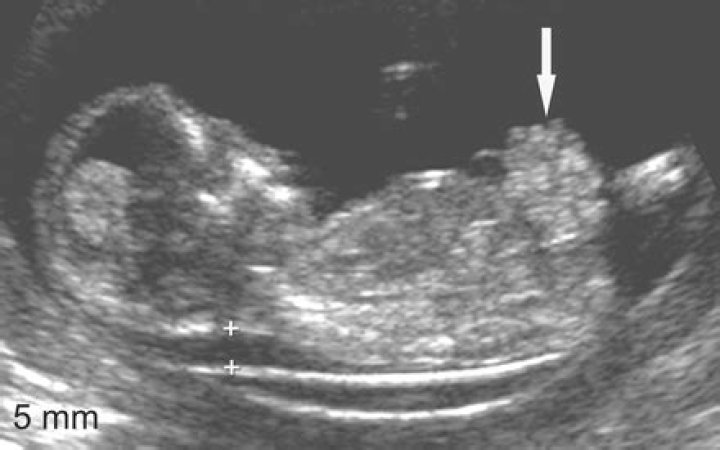

Gastroschisis can be diagnosed by prenatal ultrasound or upon birth. It is differentiated from omphalocele by the presence of freely floating abdominal organs in the amniotic cavity without a membranous covering. The organs appearing on the outer surface of the abdomen, after delivery, confirms the diagnosis.

Ultrasound Video showing a rare case of fetal anomaly called Gastroschisis.

If your baby has gastroschisis, an ultrasound may show the bowels floating outside of your baby's belly. Health care providers may find gastroschisis as early as 10 weeks of pregnancy on ultrasound, but it's most often diagnosed between 18 and 20 weeks.